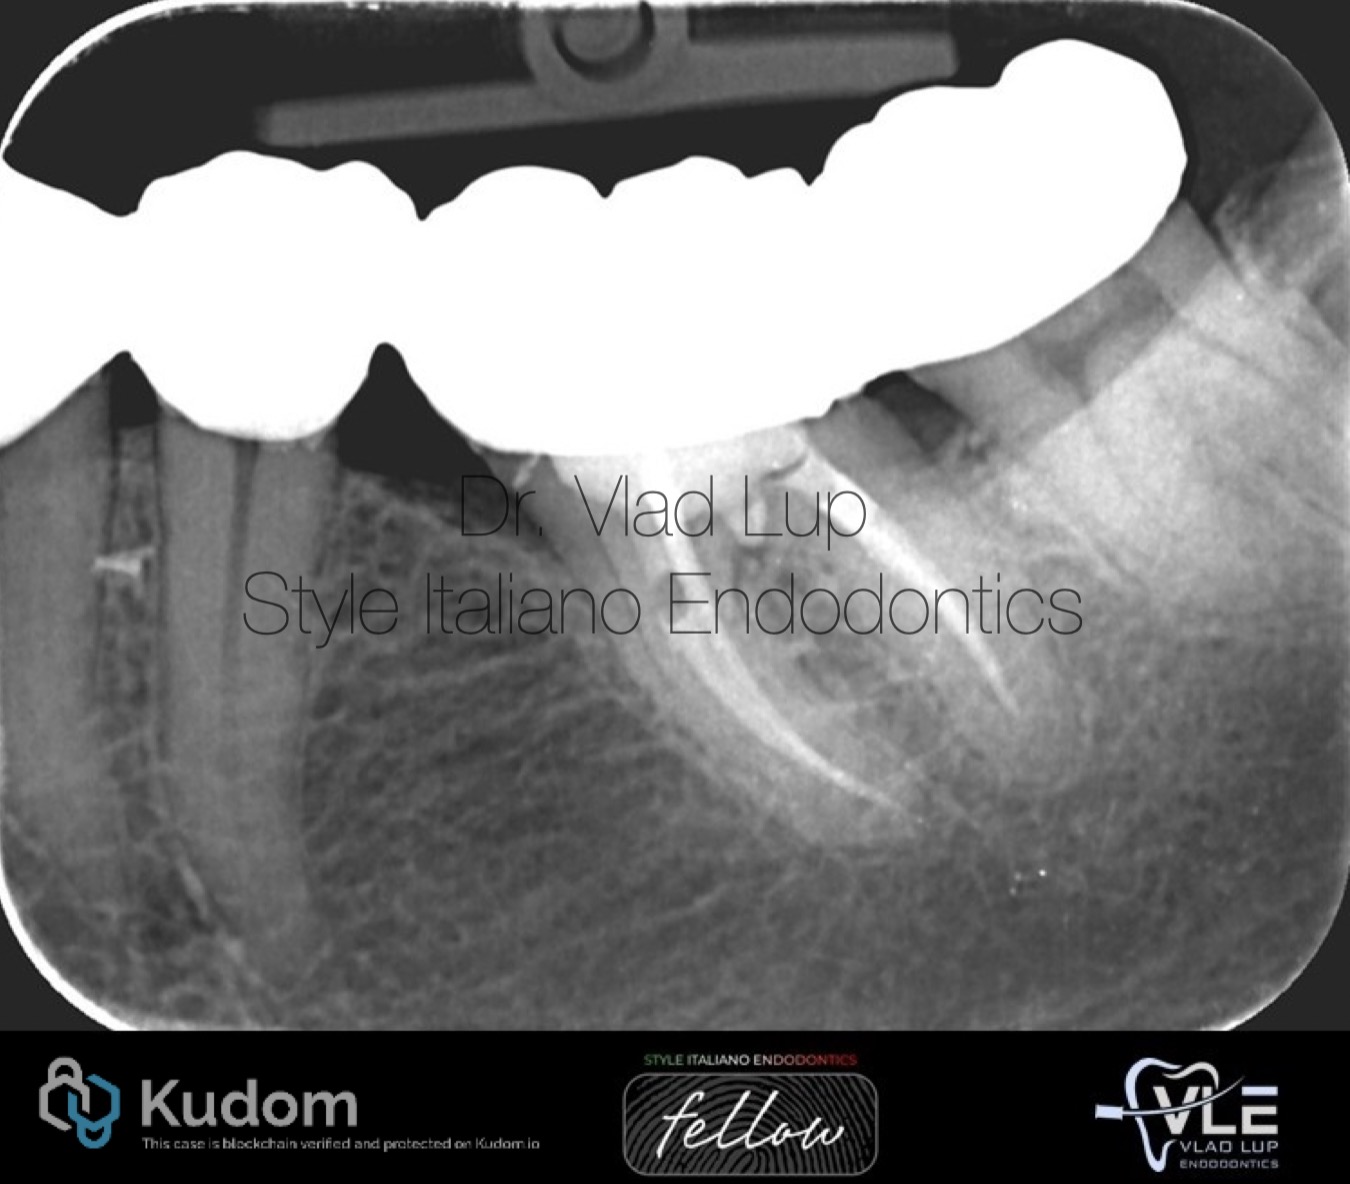

Fig. 12

The post operative radiograph shows the perforation site repaired without any extrusions. A little void in the obturation material can be seen in the mesio-lingual root canal maybe due to the ledge but considering the seal of the orifice under isolation, no problems should be expected